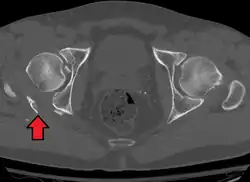

X-ray visualization is best done in Antero posterior view and Iliac and obturator oblique views. In CT scan the characteristic feature is that the fracture line runs from front to back. CT scan also helps in identifying impaction of bone pieces and if there are pieces in the joint

To understand the fracture pattern of a fractured acetabulum, it is essential to have minimum three x-ray views, though use of CT scan with 3-D reconstruction of images has made understanding of these fractures easier.

In all cases, CT scan can assist in identifying impacted bone pieces, which may be found within the joint, and MRI may be done to identify the extent of potential injury to the sciatic nerve.